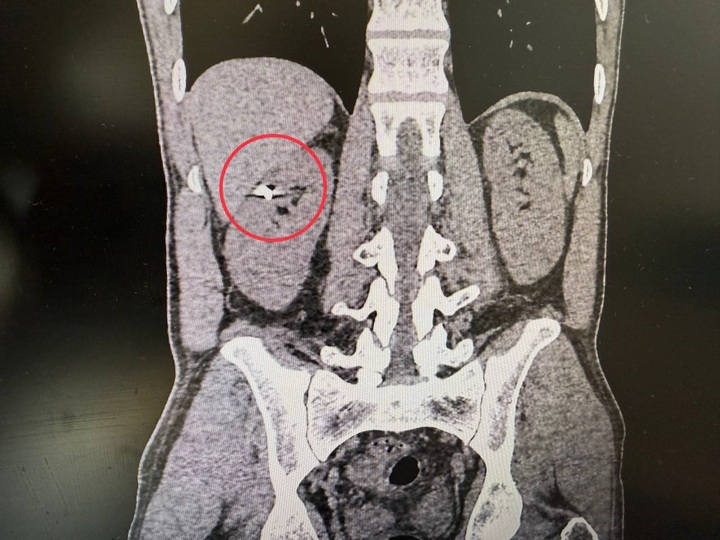

Главврач Лотошинской больницы, куда обратился пациент, направил мужчину в Истру, где его госпитализировали в урологию. На компьютерной томографии врачи зафиксировали осколок в верхнем полюсе правой почки. Печень была тесно припаяна к почке, и извлечение осколка могло привести к серьезному кровотечению и потере органа. Специалисты сделали резекцию почки лапароскопическим методом и извлекли осколок. Операция длилась около двух часов и прошла успешно: почку удалось сохранить. Сейчас пациент уже выписан.